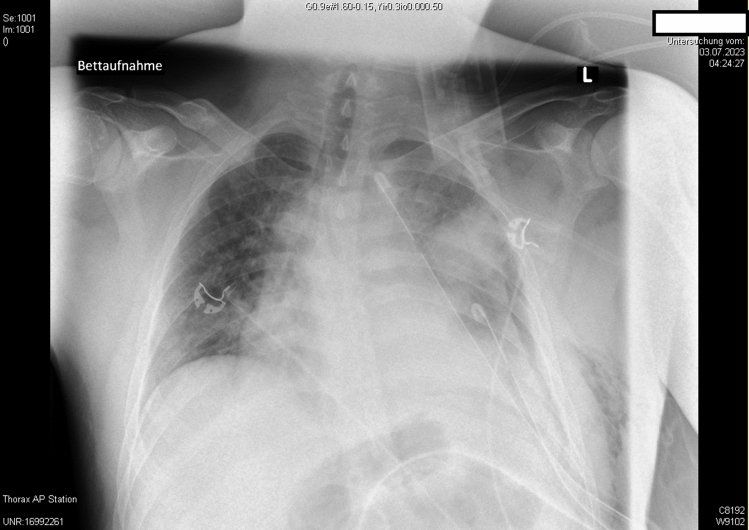

The use of veno-venous extracorporeal membrane oxygenation (VV-ECMO) has become increasingly prevalent, particularly in respiratory disease pandemics such as H1N1-influenza and SARS-CoV-2. This surge has emphasized the importance of clear therapy recommendations, improved accessibility to ECMO technology, established ECMO teams, and structured networks to ensure access to specialized care throughout the course of the disease for patients with severe ARDS. Although the initiation criteria for VV-ECMO are well defined, treatment strategies while on ECMO regarding e.g., ventilator management or ECMO weaning strategies remain variable and with lack of consensus. NAVA (Neurally Adjusted Ventilatory Assist), as an assisted mechanical ventilation modality, offers real-time electromyographic feedback, which has been shown to enhance prolonged weaning processes from mechanical ventilation. We present a case of penetrating thoracic trauma complicated by ARDS, successfully managed with VV-ECMO. NAVA was employed to monitor and facilitate ECMO. This approach integrates ECMO weaning with ventilation settings, considering both gas exchange lung function, such as carbon dioxide removal, and respiratory mechanics in the form of neuromuscular coupling. This is a new approach to VV-ECMO weaning. More research is planned to validate the efficacy of this method in conjunction with additional parameters, such as diaphragm activity evaluated sonographically in a randomized design. This case underscores the potential of NAVA in VV-ECMO weaning, offering a promising avenue for optimizing patient care and outcomes.